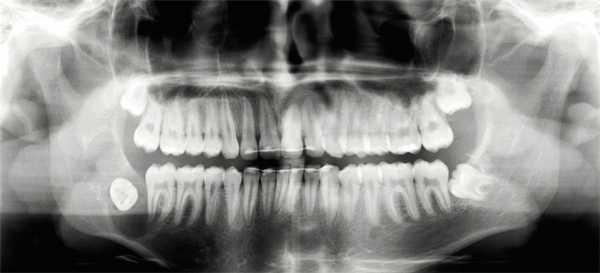

На панорамной послойной рентгенограмме (ОПТГ) в области 48 зуба мудрости определялся многокамерный очаг разрежения костной ткани с относительно четкими границами, распространяющийся до области угла и частично в область восходящей ветви нижней челюсти (рис. 1) .

Рис. 1. Рентгенограмма до операции: очаг остеолиза в области угла нижней челюсти справа, многокамерный, с относительно четкими границами. Ретенированный дистопированный 48 зуб мудрости

На рентгенограмме, изготовленной с целью контроля ортодонтического лечения 16 мес. назад, патологического процесса в области 48 зуба еще не определялось.